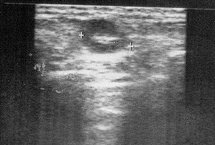

Le ganglion normal a classiquement une forme ovalaire et est surtout caractérisé par son caractère hypoéchogène contrastant avec un hile hyperéchogène. Parfois, il aura une forme plus allongée mais il ne devra pas mesurer plus de 8 mm dans son diamètre transverse.

Face à un ganglion de forme arrondi, et surtout face à la disparition de l’hyperéchogénicité du hile, on devra suspecter une lésion maligne.

A confronter aux données de l’examen clinique, bien évidemment !